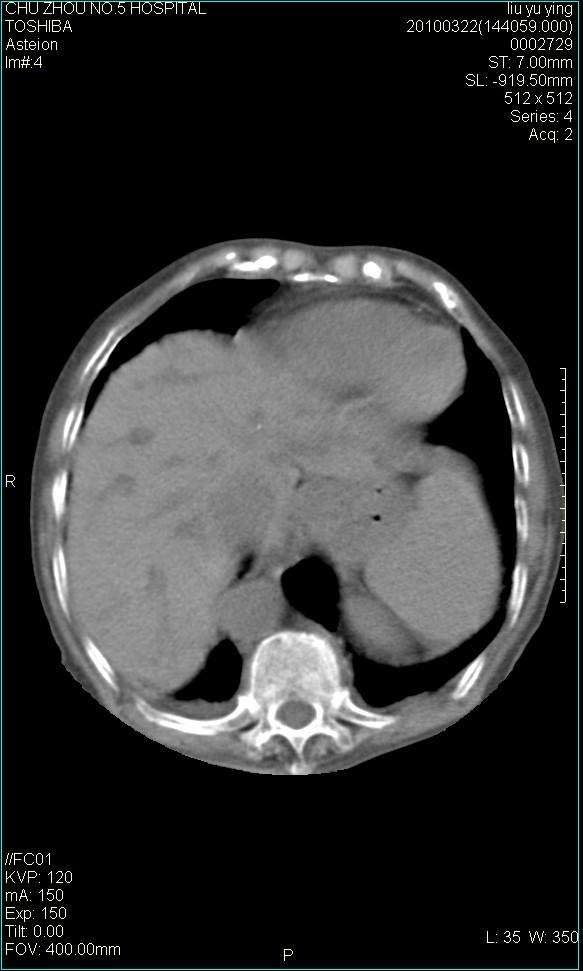

以下是引用科室第一人在2010-3-23 6:50:00的发言:[br]胆总管下段梗阻,多为肿瘤性病变,巨形胆囊,胆囊炎胆囊窝积液。[br]双侧胸腔积液,右降

以下是引用随光逐影在2010-3-23 8:12:00的发言:[br]1)胆系低位梗阻(肝内外胆管扩张,胆囊增大),原因待查。2)胆囊炎。3)双侧少量胸腔积液。4)降主动脉迂曲。